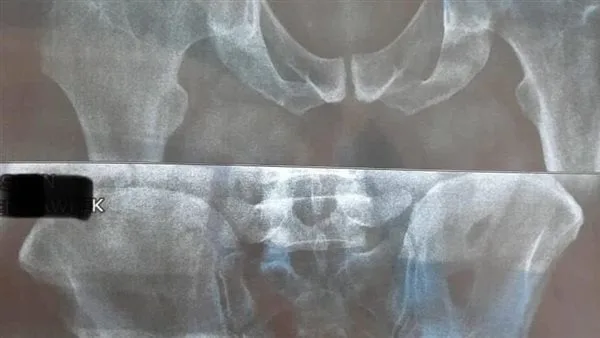

نجح فريق طبي بمستشفى الخانكة التخصصي بمحافظة القليوبية، في إجراء 30 عملية تغيير مفصل صناعي.